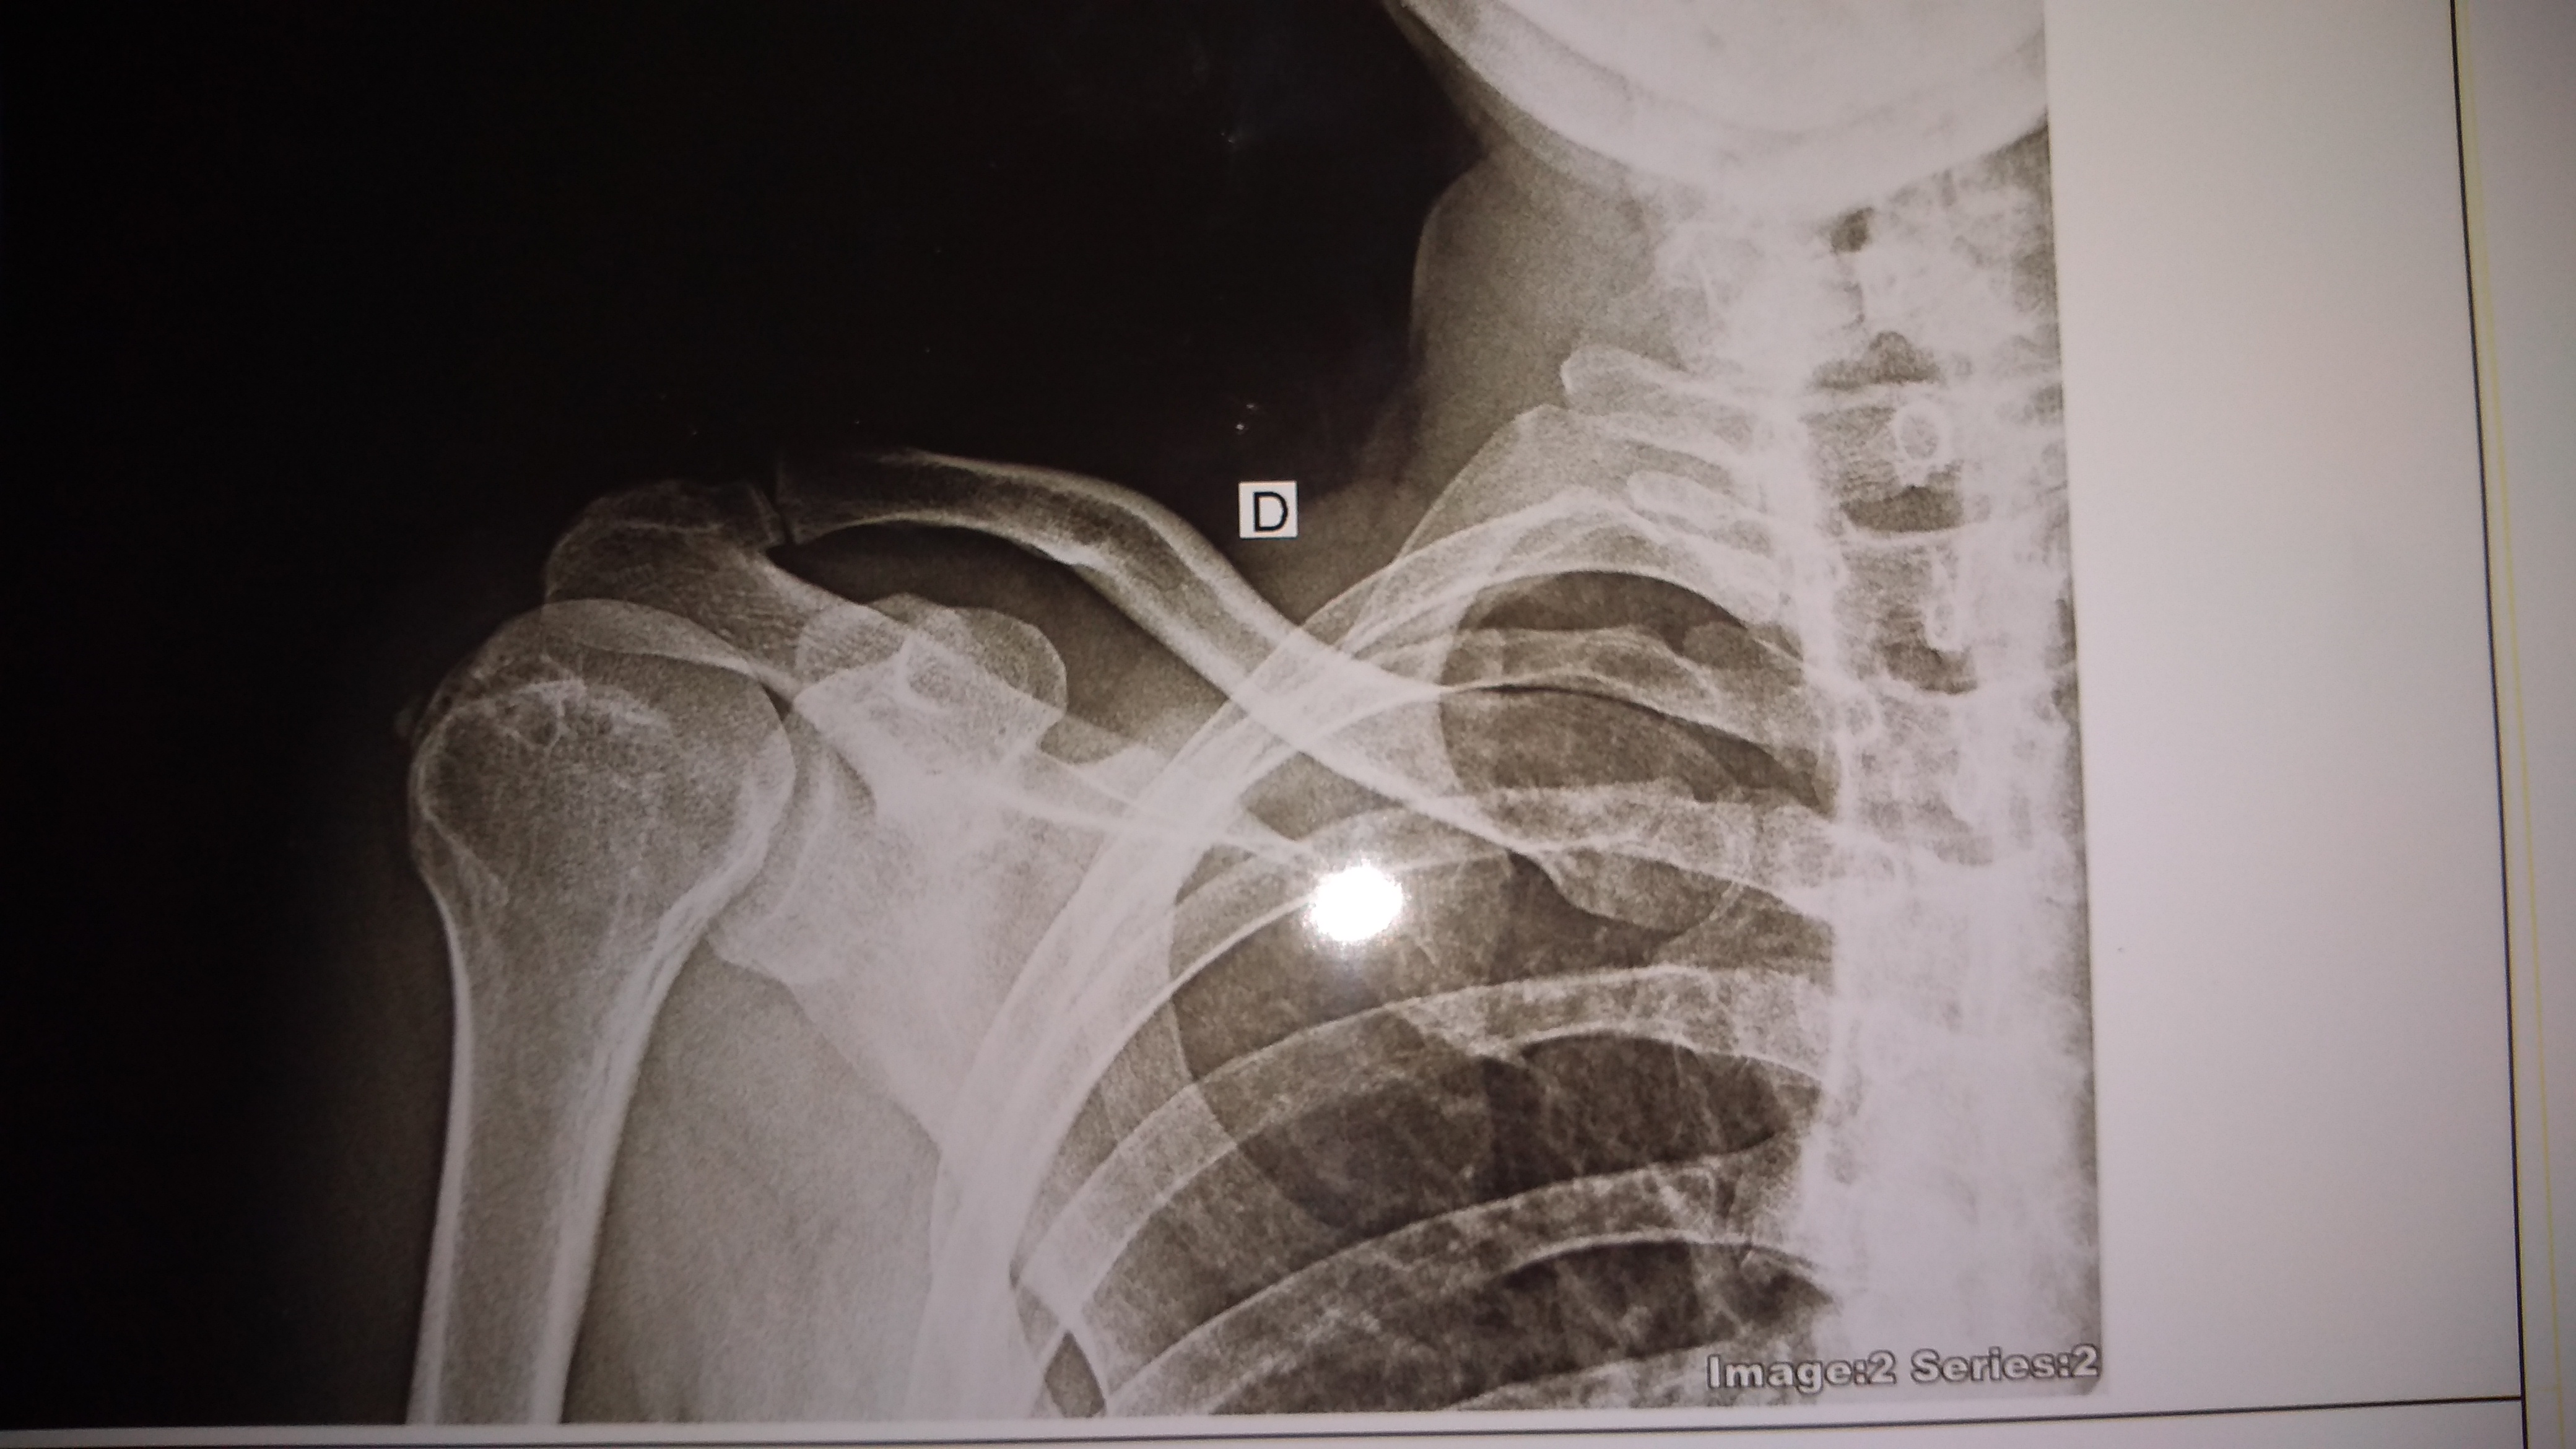

Ligamos pela quarta vez a moça apenas dizia que era pra esperar que viria, só não sabia a hora, então esperamos e esperamos….e nada!! Então mais uma ligação e a mesma coisa, mesmo informando que o paciente não podia se locomover e que precisava do atendimento com urgência mais ela dizia apenas que a ambulância estava no HGM e então indagamos sobre a motolâcia do SAMU para vim e fazer o atendimento na residência pois o paciente não conseguia sentar e nem andar e precisava dos primeiros atendimentos pois seu ombro tinha deslocado, mais a moça informou que as motolâncias só atendiam até às 18hs e que elas não poderiam ir.

Pois bem, com isso ele ficou umas três horas girando de dor a espera do Samu que nunca veio, foi onde ele recebeu ajuda de amigos que o colocaram dentro de um carro e o levaram até o HGM de Codó e quando chegamos lá não havia nenhuma ambulância do SAMU no local, e ao chegarmos em casa por volta das 23hs fomos informados que a tal ambulância nunca havia aparecido na residência do paciente, se o paciente não tivesse recebido ajuda, ele ainda estaria esperando pelo SAMU ou teria morrido já que o braço do paciente tinha sido deslocado e ele não aguentava de tanta dor.